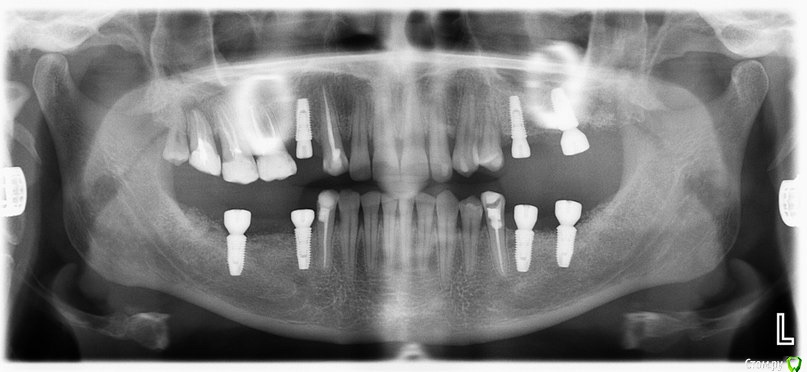

Доброго времени суток коллеги, сразу извиняюсь за качество фото т.к. фотографировал на тапок. Вот такая ситуэшн, на днях ко мне попала пациент от коллеги с окклюдатором в руках, где загипсованы модели в привычном прикусе. Там где отмечены красные точки, стоят уже формирователи. Сделал оптг, забрал модели.

На сегодня имеем феномен Попова-Годона в области 1.6, 1,7, стираемость нижних резцов, глубокое резцовое перекрытие. Думаю, что все это связано с длительным отсутствием жевательных зубов.

По снимку явно дегенеративные изменения сустава, бугорка почти нет, поэтому я думаю можно было бы, для начала попытаться поднять высоту на имплантах используя временные абатменты и времянки. Сможете поднять прикус на необходимую высоту + частично попытаться устранить феномен попова-годона (если зубы оставлять), за одно понаблюдаете, как на это отреагирует сустав. На мой взгляд при таком состоянии сустава даже с лицевой дугой будет проблематично идеальное определение ЦС ИМХО. Все остальное на времянках думаю до года. И на ОПТГ надо было сережки снять :rolleyes:  ;) . Можно сразу уменьшить высоту 1.6,1.7, учитывая карман глубокий за 1.7, а можно все их убрать (1.9,1.8,1.7,1.6) и поставить импланты(меньше геморроя) :)